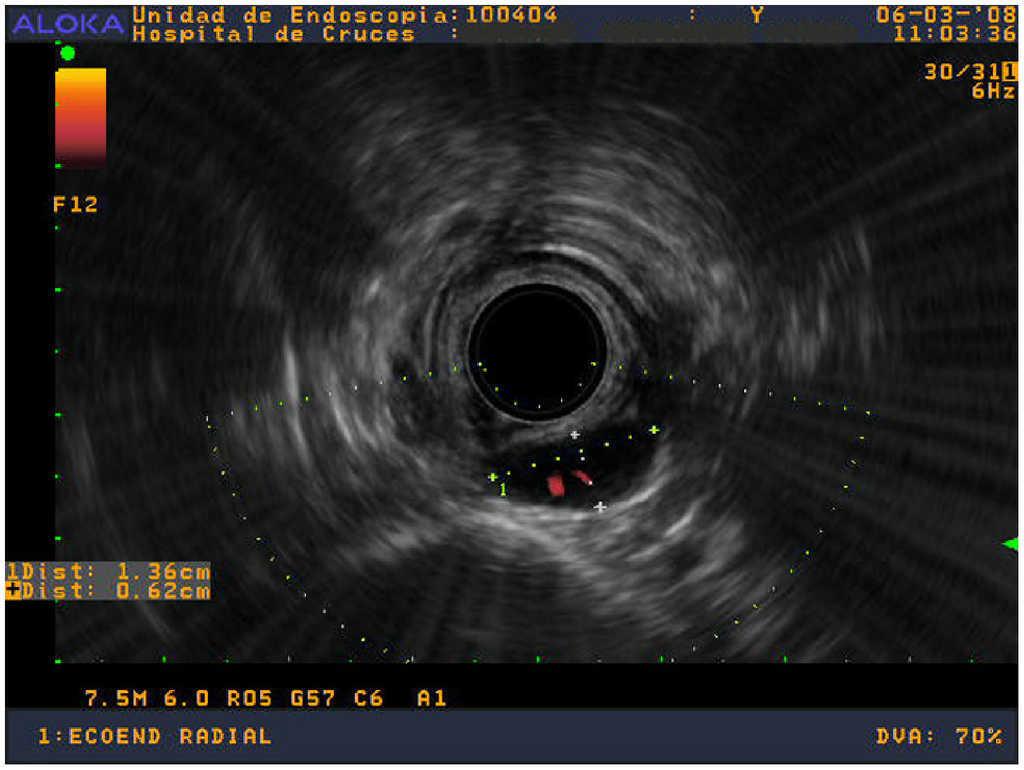

Paciente con gammagrafía paratiroidea con 99Tc-sestamibi positiva en el área inferior derecha, intervenido en otro centro y remitido con una TC en la que aparecía una imagen compatible, en mediastino superior, apoyado en la columna. La ecoendoscopia confirmó lesión compatible retroesofágica en mediastino superior, a 19 cm de la arcada dentaria, apoyada en el cuerpo vertebral (fig. 3). Durante la intervención se halló y se extirpó en la localización descrita un adenoma de 800 mg.

Figura 3. Ecoendoscopio radial; delante del cuerpo vertebral y posterior al esófago se aprecia una imagen hipoecoica, bien definida, de 1,36×0,62 cm. El Doppler muestra arteriolas en su interior.